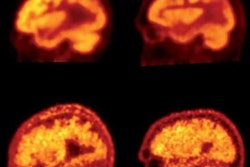

Wong and colleagues found that peak standardized uptake values (SUVpeak) were highest with F-18 RO-948 across all brain regions and among all subjects. In light of that trend, they performed a voxel-wise and region-based analysis of F-18 RO-948; it showed multiple areas with statistically significant differences in tau binding between Alzheimer's patients and healthy controls. The voxel-wise analysis also identified a set of symmetric clusters where Alzheimer's patients had statistically significant greater binding than healthy controls (p < 0.001, cluster size > 50).

An analysis of variance (ANOVA) among 22 high tau-binding regions further revealed 13 areas (60%) with statistically significant differences in tau binding between the two groups (p < 10-5). In short, F-18 RO-948 outperformed the other two prospective tau tracers in the study and compared "favorably with other existing tau PET tracers," the researchers wrote.